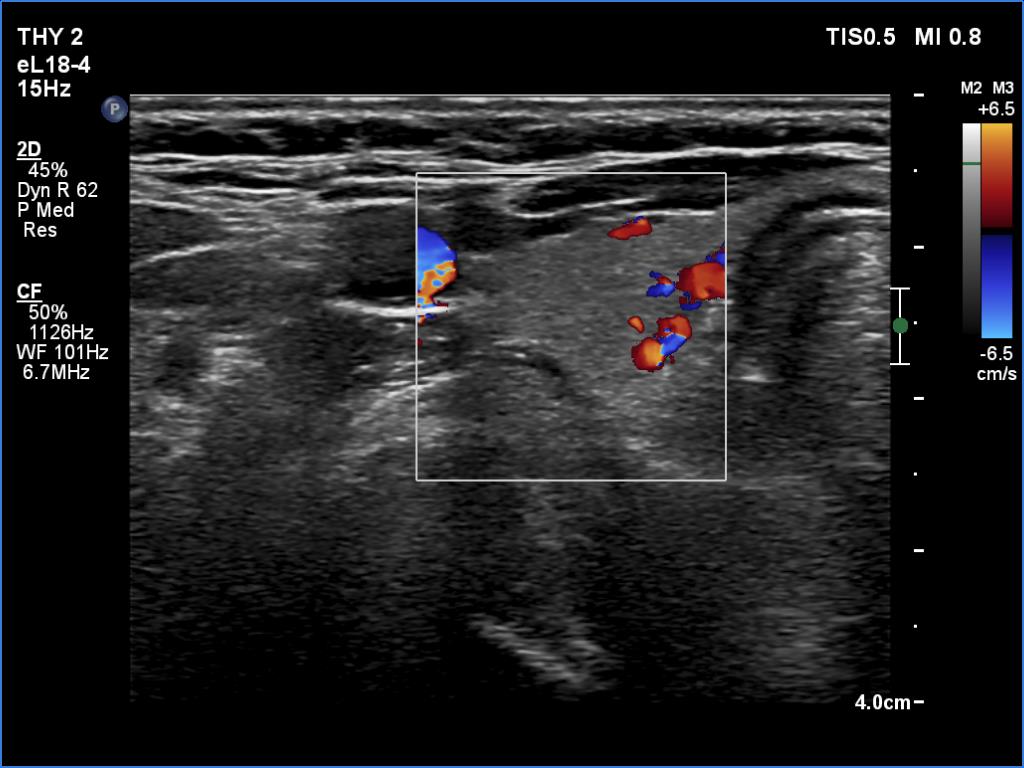

Second examination 6 month later (2nd row of images)

Clinical presentation. The patient was referred for evaluation of hyperparathyroidism. Elevated calcium and parathyroid hormone levels were found during the first evaluation. (These findings were not yet available when I first examined the patient.) Further evaluation disclosed a hyperfunctioning right lower parathyroid. The patient was operated on but no parathyroid tissue was found on histopathology. (A more experienced parathyroid surgeon was quarantined at the scheduled time of the operation, so a less experienced colleague performed the surgery.) Both hypercalcemia and hyperparathyroidism have persisted.

Laboratory tests: parathormone 129 pg/ml (normal value: 12-88), serum calcium 2,89 mM/L, phosphate 0,71 mM/L.

Ultrasonography revealed a hypoechoic mass corresponding to the right lower parathyroid.

Cytology resulted in benign lesion, a pattern which corresponded to a parathyroid adenoma.